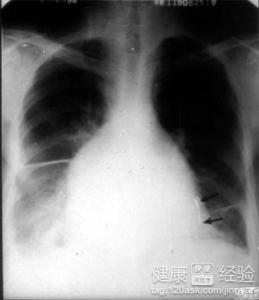

如何治療小兒限制型心肌病

兒子這幾天有些不對勁,老是捂著胸口,動都不想動,問他的時候就說他心很痛,我覺得很擔心,於是就帶他去醫院檢查,才知道是得了小兒限制型心肌病,要兒子接受治療,給大家講講治療過程吧。

1 醫生檢查完兒子以後,就開始讓護士准備血管擴張藥,目的是為了讓兒子的心血管順暢運轉,注射了以後,兒子安靜很多,也不吵著說不舒服了。

2醫生讓兒子留院查看,每天都要觀察他的病情,每天都要注射血管擴張藥,兒子也因此好很多了,於是醫生開始准備口服洋地黃制劑,讓兒子每天早晚各服一劑,慢慢地感覺好很多了。

3就快痊愈的時候,醫生讓兒子在住院的最後幾天每天注射抗凝劑,為了防止他的限制性心肌病復發。出院後,也沒見他復發過,效果真的很好!